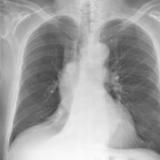

RLL Collapse 3 PA only

Date: 02/28/2004

Views: 3181